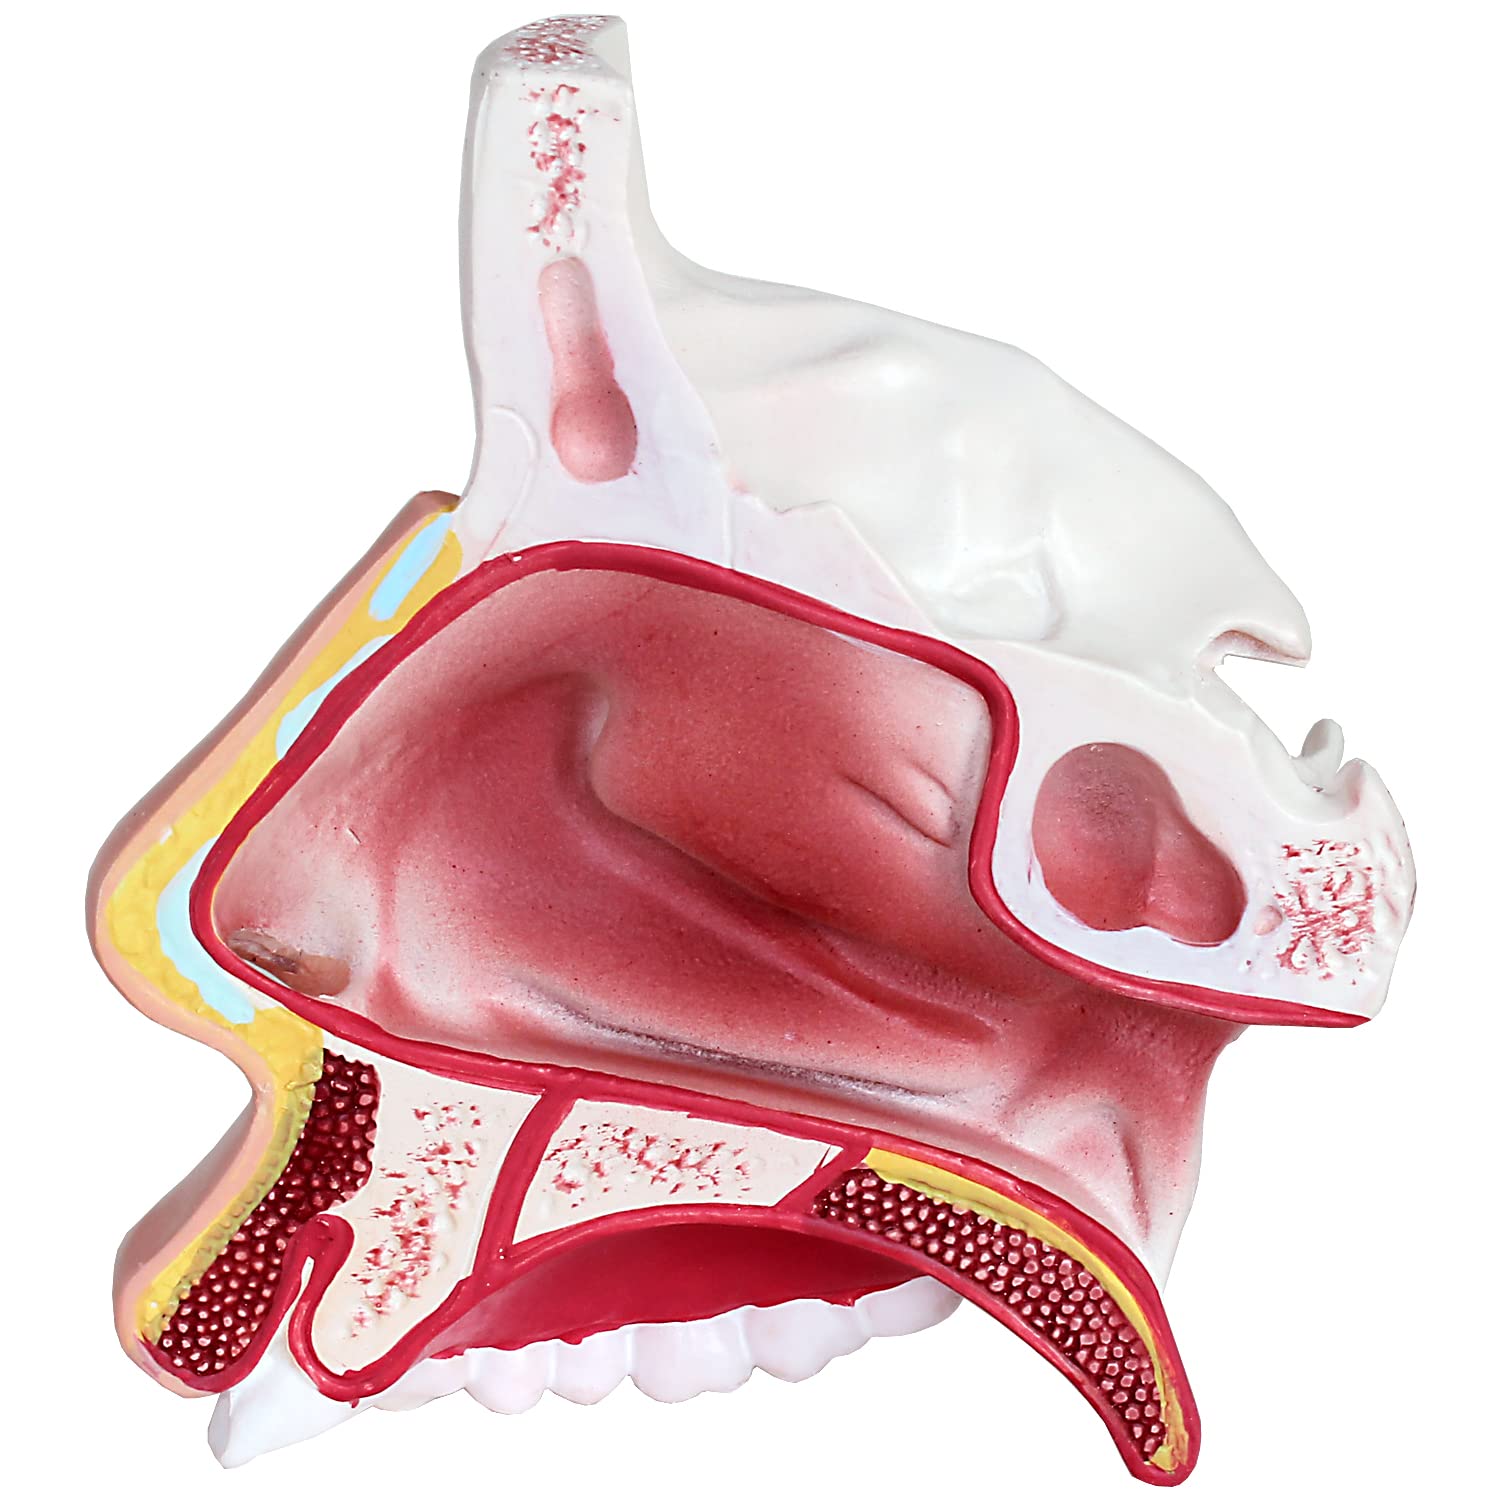

Nasenhöhle - Anatomie, Histologie & Polyposis nasi | Kenhub

Nasenhöhle – Wikipedia